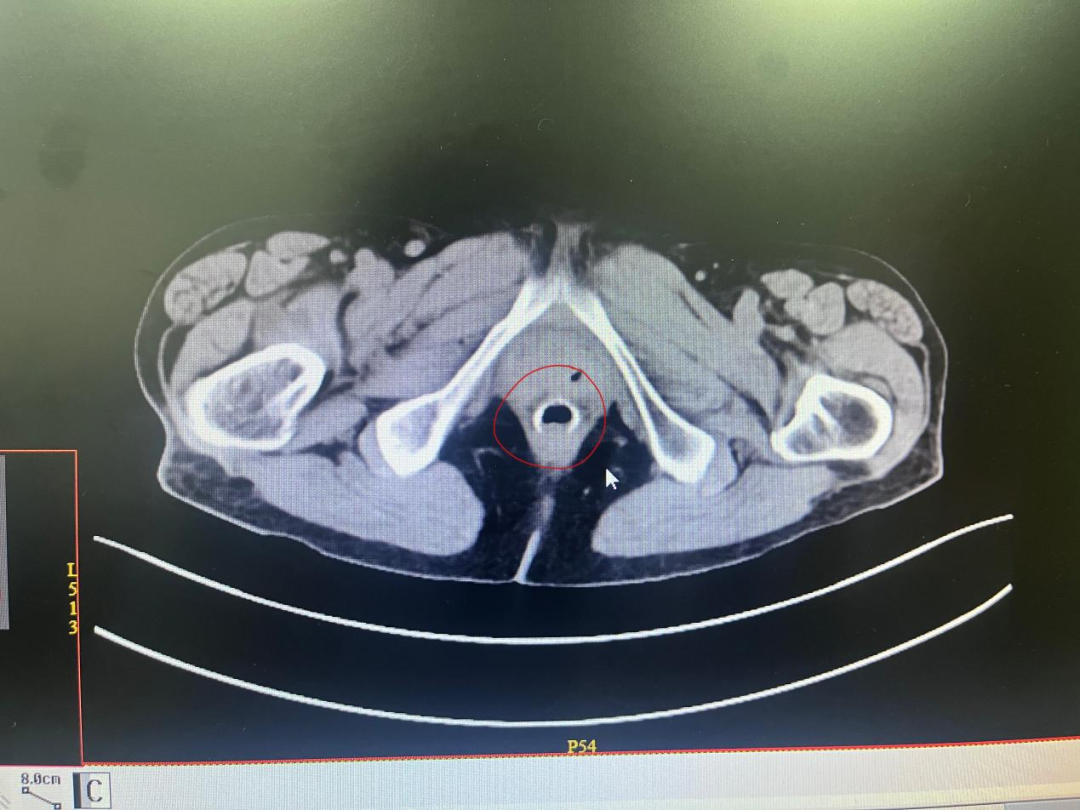

CT确证:随即进行了CT检查——在手术吻合区域,赫然可见数枚金属吻合钉未能正常脱落吸收,形成了明显的局部刺激和炎症病灶,这正是导致王奶奶反复刺痛的"罪魁祸首"。